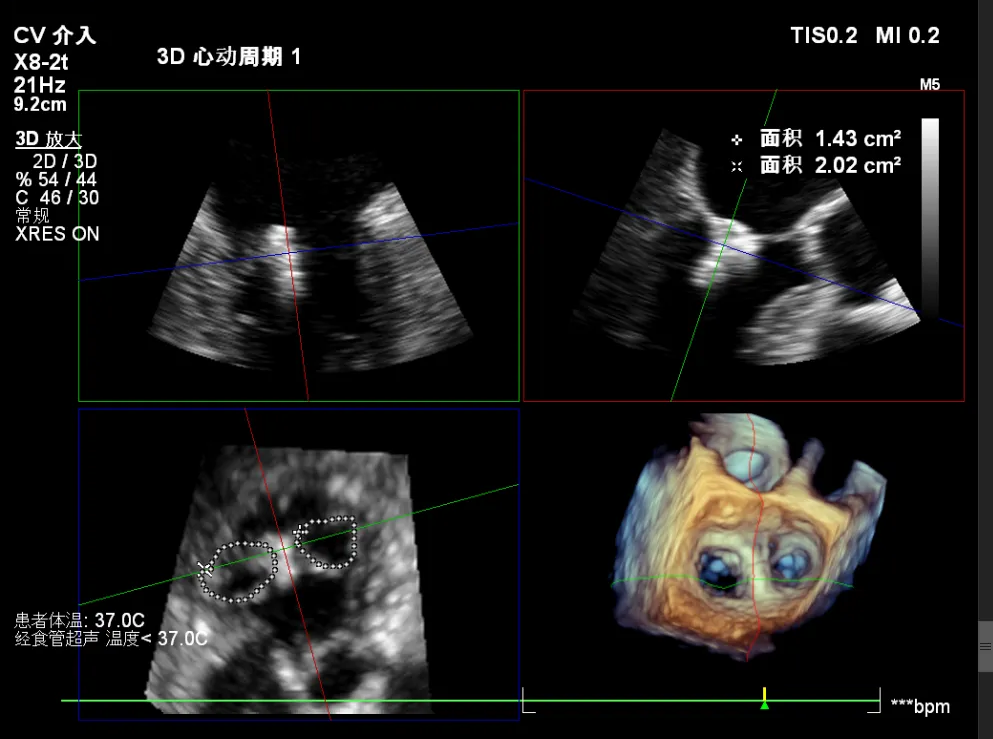

患者为原发性二尖瓣反流(DMR),收缩期可见二尖瓣反流信号,反流位于 2 偏 3 区,基线期二尖瓣反流程度4+。

前叶长度 15.7mm,后叶长度 12.7mm,后叶脱垂宽度13.9mm,脱垂高度4.76mm, 瓣环直径37.1mm,VC:4*7mm, MVA约4cm² 。瓣叶质地较差,腱索断裂、后瓣叶脱垂。

术前超声